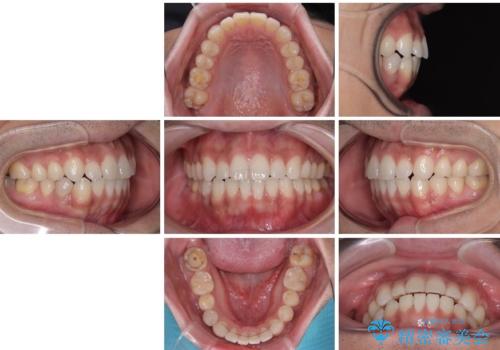

目立たない装置でデコボコを改善 ハーフリンガルによる矯正治療

一年と数か月で矯正を終えることができました。

下顎前歯部には後戻り防止のワイヤーを装着しています。